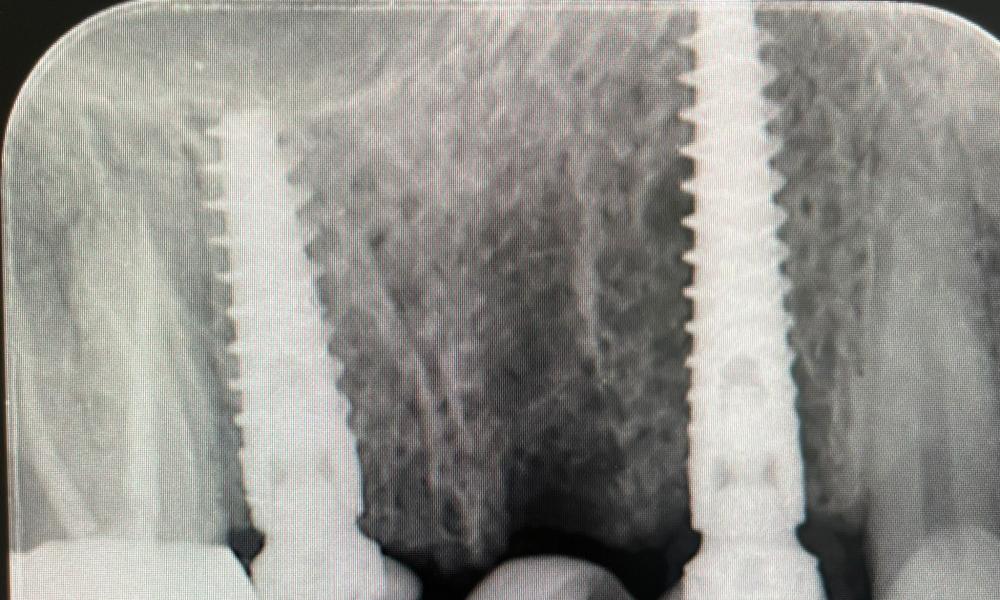

Impianti a carico immediato, di cosa si tratta?

Recuperare il sorriso in tempi rapidi è possibile! Ma quali sono le

caratteristiche e i vantaggi di questa tecnica?

Presso lo Studio Dentistico Zambon siamo specializzati in trattamenti avanzati come il postestrattivo con carico immediato, un intervento innovativo che consente d

Innovazione e Precisione: Gli Impianti Dentali Angolati a Padova

Allo Studio Dentistico Zambon di Padova, siamo sempre all'avanguardia nelle tecnologie odontoiatriche per offrirvi il massimo comfort e precisione nei trattamenti.